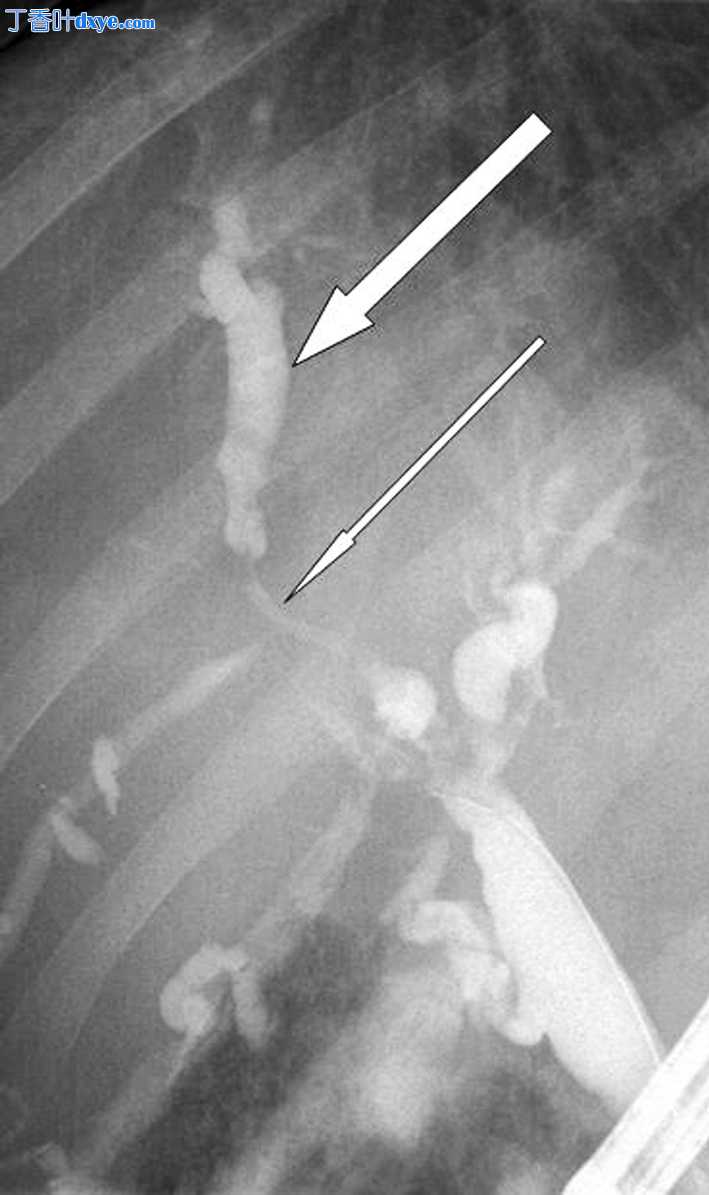

进行了内镜逆行胰胆管造影(ERCP),结果显示右肝管节段性狭窄伴狭窄后扩张(图 2)。 胆管内没有结石。 机械扩张右肝管的主要狭窄,将鼻胆管引流管和胆管支架置入右肝叶。 胰管正常。

图 2

ERCP 显示右肝管节段性狭窄(细箭头)伴狭窄后扩张(粗箭头)